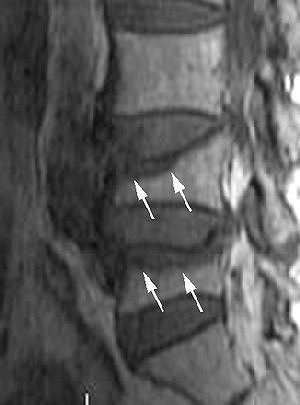

The MR images were reviewed by Tanigawa's co-authors, Dr. Koshi Ikeda, Ph.D, and Dr. Naoto Omura, both neuroradiologists. Regions that exhibited signal intensity lower than that of fatty bone marrow on T1-weighted images and higher than fatty bone marrow on T2-weighted images were indicative of edema, according to the study's classification system.

- Group 1, type 1: bone marrow edema present in 50% or more of the vertebral body

- Group 2, type 2: bone marrow edema present in less than 50% of the vertebral body

| Sagittal T1-weighted (above) and fat-suppressed T2-weighted (below) MR images of osteoporotic compression fracture of L4 and L5 vertebral bodies with considerable bone marrow edema pattern in a 74-year-old woman. Regions of low signal intensity (arrows) are present in the anterosuperior portion of L4 and L5 in image above and occupy less than 50% of the vertebrae. Regions of high signal intensity (arrows) are seen in the anterosuperior portion of L4 and L5 in image below. The high signal intensity regions occupied less than 50% of the vertebrae (group 2). |